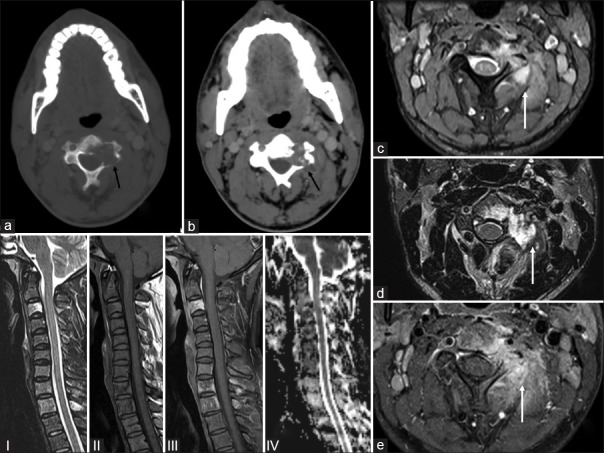

| Figure 3:Guided lesional biopsy of the lytic lesion present in the C3 vertebra in a 28-year-old man: (a) Varying proportions of Langerhans cells, multinucleated giant cells (arrow head), eosinophils, and small lymphocytes (H and E, ×40). (b) Numerous eosinophils with formation of eosinophilic microabscesses (arrow heads) (H and E, ×100). (c and d) Langerhans cells exhibiting moderate degree of cytologic atypia with dented, folded, and grooved nuclei (arrow heads). Neutrophils and eosinophils (arrows) are also seen accompanying the Langerhans cells (H and E, ×200). (e and f) Fine-needle aspiration: Langerhans cells (arrow heads) having abundant pale to intensely eosinophilic cytoplasm with oval nucleus and prominent longitudinal grooving. Few eosinophils (arrow) are seen scattered in the background (H and E, ×400)